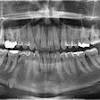

Dentists Debate Need To Extract Wisdom Teeth Los Angeles Times

Dentists Debate Need To Extract Wisdom Teeth Los Angeles Times from ca-times.brightspotcdn.com